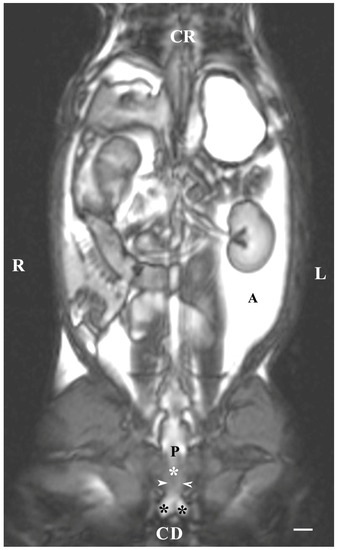

On transverse T2-weighted imaging in the corresponding planes (first caudal vertebra, then the plane between the first and second caudal vertebrae—dorsal; the caudal part of the pelvic symphysis—ventral; the plate of ischium—lateral), the rabbit bulbourethral glands were identified. They appeared as soft-tissue, homogeneous organs with hyper-intense characteristics compared to the peripheral soft tissue landmarks (urethra, rectum, pelvic diaphragm), except for the penile bulb and the beginning of the penile root. The latter were visualized as findings with the highest intensity relative to structures in the perineum. The shape of the glands was oval. The glandular capsule was differentiated as a hypo-intense peripheral ring-like finding. The ventrally located pelvic part of the urethra was hypo-intense and imaged dorsally to the caudal part of the pelvic symphysis. The rectum showed a hypo-intense image that was localized dorsally to the penile bulb and root and ventrally to the first caudal vertebra (Figure 1).

Figure 1. T2-weighted transverse image of rabbit pelvis in the plane through the level of the first caudal vertebra (white star): R—right; L—left. Bulbourethral glands (white horizontal arrows), the pelvic part of the urethra (white cross), penile bulb (B), rectum (R), ischial bones (black stars), the caudal part of the pelvic symphysis (white perpendicular arrow), pelvic diaphragm (black inclined arrows), and testes (T). Line—10 mm.